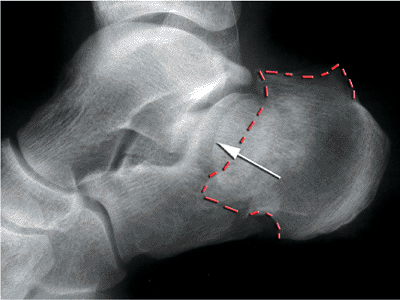

![]() |

Figure 35.8. Plain radiographs of a joint depression fracture. The depressed joint fragment (white arrow)

is impacted below the stable medial fragment. This creates a double density. The impaction of the posterior tuberosity is noted by the dotted red line. |